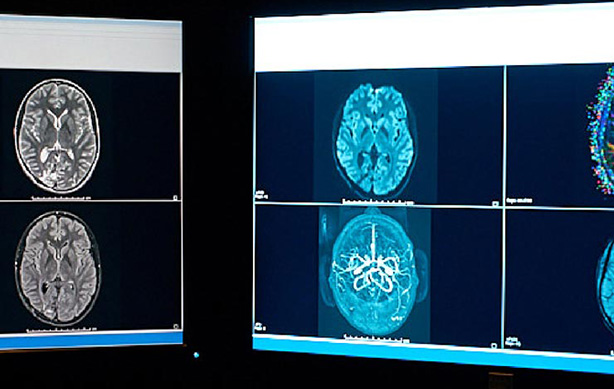

ChRIS project brain scans on computer monitors ChRIS project brain scans on computer monitors

除了省時,AI 還可助放射科醫師拯救性命

ChRIS Research Integration Service 是一種開放原始碼影像處理平台,使用開放雲端的軟體和運算基礎架構。由於採用開放原始碼,因此來自世界各地的人們都能貢獻一己之力;加上 Red Hat 將原始碼開放共享,該團隊得以更輕鬆地建構、部署和擴展在敏捷雲端基礎架構上的影像、分析和診斷應用程式。

進一步了解 ChRIS